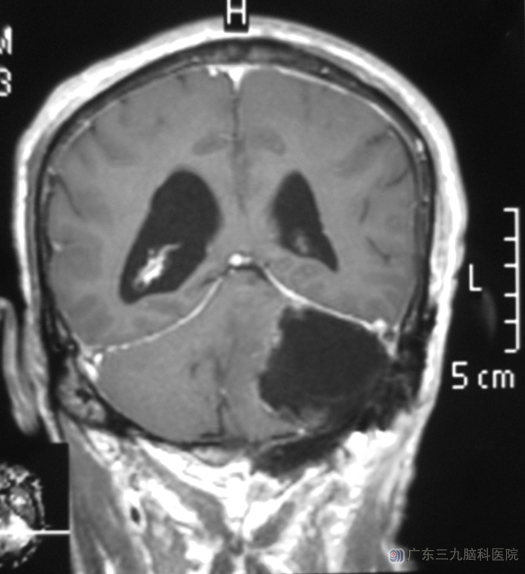

由综合神经外科 鲁明主任主刀,在全麻下行左侧脑室后角外引流术+左侧桥小脑角脑膜瘤切除术,显微镜下见肿瘤与小脑粘连,基底部位于前方硬脑膜,沿前方岩骨硬膜见前下方受压三叉神经及面听神经,镜下完整切除幕下肿瘤,神经均保护完好,手术顺利。经过治疗,荣先生已康复出院。病理结果为:过渡型脑膜瘤(WHO I级)。

▲手术后